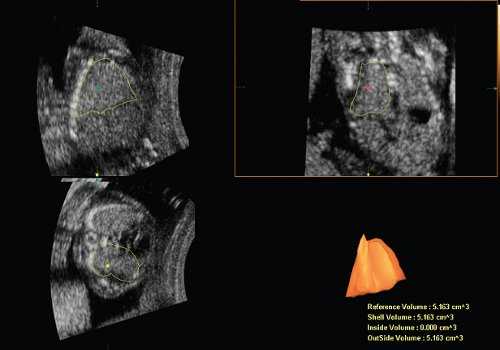

Объем легких теоретически можно оценить в режиме 2D, однако с введением в клиническую практику новых ультразвуковых технологий появилась надежда, что теперь это измерение можно делать точнее и проще. Действительно, использование программы VOCAL (Virtual Organ Computer-aided AnaLysis) позволяет получить фактически виртуальный "слепок" легких (рис. 1). Для этого объем грудной клетки следует получить в 3D режиме в сагиттальной плоскости, когда плод расположен лицом к датчику. Желательно соблюдать следующие правила: датчик слегка наклонить к голове для лучшей визуализации диафрагмы, использовать высокое качество изображения и гармоники, величина угла захвата изображения от 40 до 85º в зависимости от срока.

Рис. 1. Реконструкция здорового правого легкого и расчет его объема с применением программы VOCAL.

Далее формирование объемного изображения необходимо производить путем последовательных поворотов изображения легкого, каждый из которых составляет 30º. Ось вращения должна проходить через верхушку легкого и точку, максимально близкую к диафрагме. Контур легкого лучше обводить вручную. Стартовой позицией для вращения следует выбирать максимальный переднезадний диаметр легкого [2].